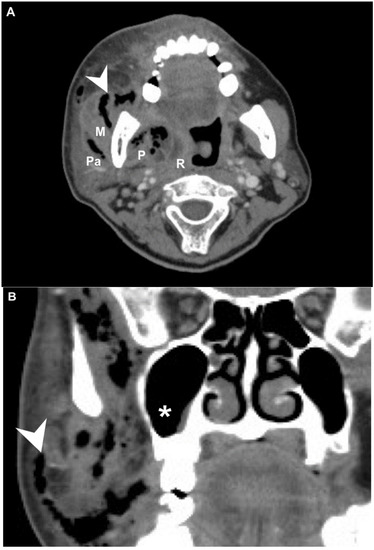

- Kim, Y.J.; Kim, J.D.; Ryu, H.I.; Cho, Y.H.; Kong, J.H.; Ohe, J.Y.; Kwon, Y.D.; Choi, B.J.; Kim, G.T. Application of radiographic images in diagnosis and treatment of deep neck infections with necrotizing fasciitis: A case report. Imaging Sci. Dent. 2011, 41, 189–193. [Google Scholar] [CrossRef] [PubMed][Green Version]

- Becker, M.; Zbaren, P.; Hermans, R.; Becker, C.D.; Marchal, F.; Kurt, A.M.; Marre, S.; Rufenacht, D.A.; Terrier, F. Necrotizing fasciitis of the head and neck: Role of CT in diagnosis and management. Radiology 1997, 202, 471–476. [Google Scholar] [CrossRef] [PubMed]